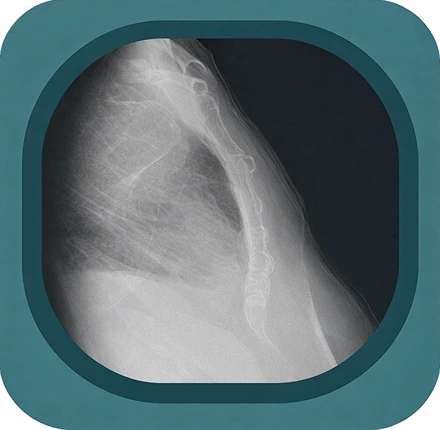

Explore high-quality X-ray anatomy from head to toe. Our database features carefully labelled images to visualize fine structures—perfect for radiologists, students, and surgeons.